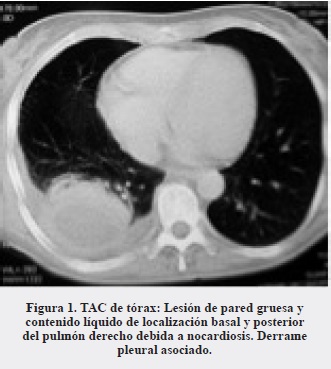

Se trata de una mujer de 48 años de edad, ama de casa, procedente del área rural de Arauquita (Arauca), VIH negativa, sin antecedentes patológicos de importancia, que consultó inicialmente al Hospital Erasmo Meoz de Cúcuta por tos, expectoración de color marrón y pérdida de peso con dos semanas de evolución. Entre el 13 de marzo y el 23 de diciembre de 2011 estuvo hospitalizada en cuatro oportunidades, en la primera por un proceso infeccioso neumónico, en la segunda por persistencia de la infección pulmonar, presencia de abscesos de tejidos blandos y artritis séptica de cadera derecha; en esta hospitalización se diagnosticó la nocardiosis diseminada debido al aislamiento de Nocardia spp. del cultivo de masa pulmonar. En la tercera hospitalización se encontró afectación encefálica además de pulmonar y requirió una cuarta hospitalización por persistencia de la infección del sistema nervioso central y por la diseminación al ojo izquierdo. En la Tabla 1 se detallan las principales manifestaciones clínicas, los hallazgos de los exámenes paraclínicos y la terapia utilizada. Las imágenes diagnósticas de las lesiones pulmonares y encefálicas se presentan en las Figuras 1, 2 y 3. La paciente finalmente mejoró de su cuadro clínico y quedó como secuela la pérdida de la visión por el ojo izquierdo.

La infección pulmonar por Nocardia es poco frecuente pero grave, especialmente en el paciente inmunosuprimido. Se puede confundir con otras enfermedades supurativas del pulmón y con enfermedades malignas. La enfermedad pulmonar es la forma de presentación clínica más común de la nocardiosis y representa el 40% de los casos. De estos, aproximadamente en 90% es causada por miembros del complejo Nocardia asteroides. Se presenta como una neumonía aguda, frecuentemente necrotizante y asociada con cavitación, como observamos en nuestra paciente (9). Otras presentaciones clínicas incluyen nódulos pulmonares indolentes de agrandamiento progresivo o neumonía asociada con empiema. Los pacientes pueden presentar fiebre, escalofríos, tos productiva, suduración profusa, pérdida de peso, anorexia, disnea y hemoptisis. Estos síntomas son también frecuentes en las infecciones por micobacterias y por Actynomices. El patrón radiológico incluye nódulos, infiltrados neumónicos reticulonodulares o difusos, abscesos simples o múltiples y áreas de consolidación con o sin cavitación (Figura 1). Frecuentemente, hay diseminación hematógena especialmente al SNC (33% de los casos), como la presentada en nuestra paciente (Figuras 2 y 3). Por ello, todo paciente con nocardiosis debería tener imágenes del SNC para investigar siembras en ese lugar. En estos casos, los pacientes presentan signos de sepsis, hipertensión intracraneana o hallazcos focales neurológicos, como en nuestro caso, que consultó por convulsiones (9). En Colombia se han informado casos de nocardiosis del SNC en sus diferentes formas de presentación clínica (11-14).